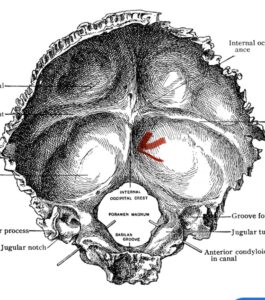

Although some patients do not require a decompression and just require an occipital cervical fusion, most require some sort of decompression of the neural elements. After a decompression an instrumented fusion is performed. A useful anatomic structure for anchoring the top portion of the construct to the skull is the midline keel of the subocciput. This structure extends from the external occipital protuberance, which corresponds to the confluence of the sagittal and transverse sinuses, to just above the foramen magnum:

(Fig. 1). This bone is quite thick, about 15 mm (Figs. 2a and b). Most modern plate systems utilize three midline keel screws with the option to place within a 2 cm lateral fixation point. This plate is connected to sometimes tricky-to-bend rods and connected to screw fixation points in the cervical spine (Fig. 3). Bone graft material extends from skull to cervical spine.

Fig. 1: Diagram of occipital bone to foramen magnum. Note external occipital protuberance (red arrow)